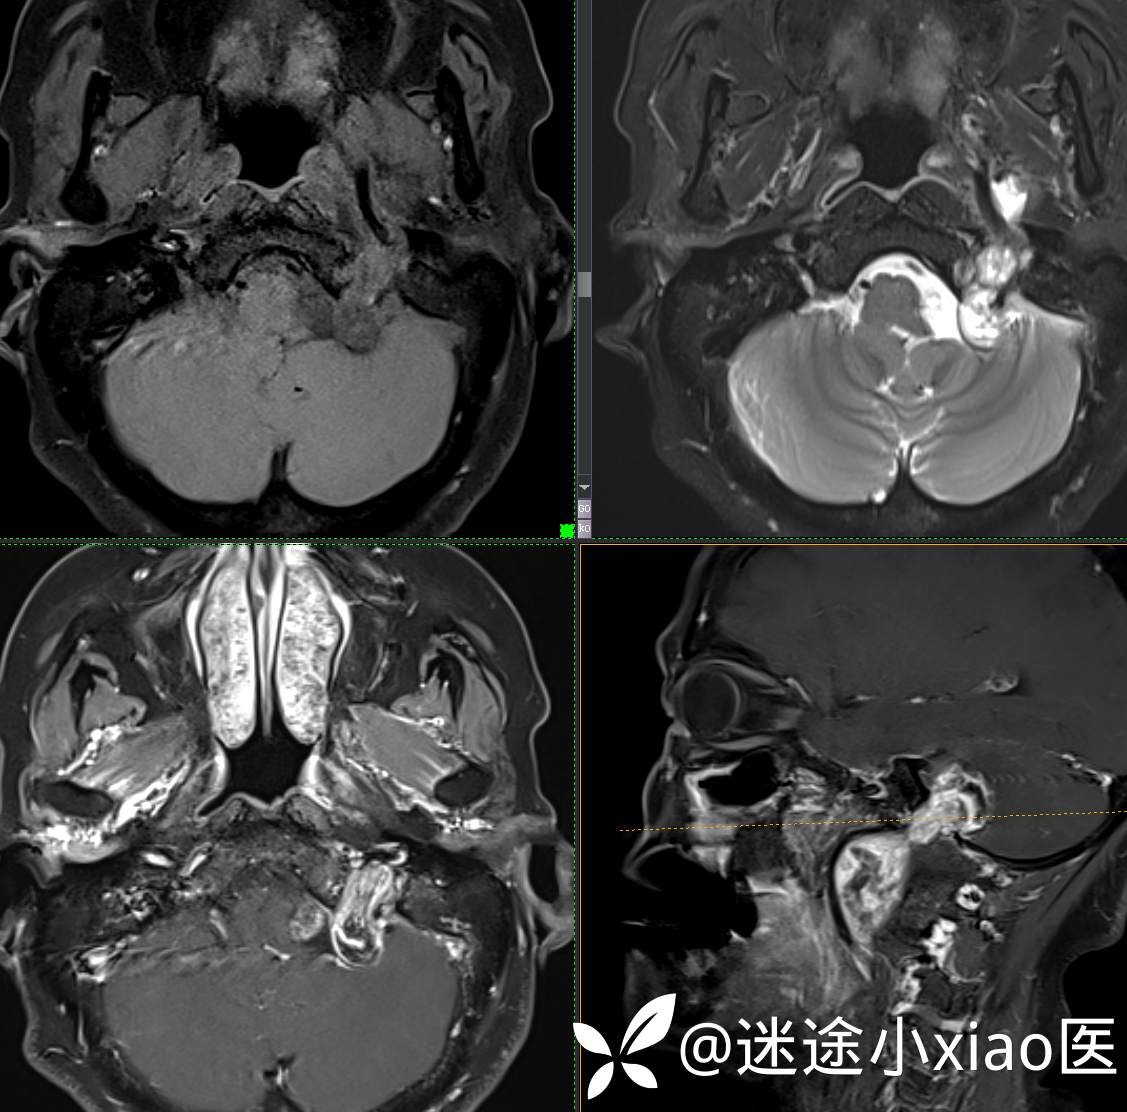

头颈组17:颈静脉孔区占位,副神经节瘤?神经鞘瘤?脑膜瘤?

患者性别:女

患者年龄:57岁

主 诉:  声音嘶哑进食困难伴左侧颌部麻木半年

现病史:  【患者半年前无明显诱因出现声音嘶哑,进食困难,只能进食糊状食物,伴有恶心呕吐,无明显头痛头晕,未加重视。